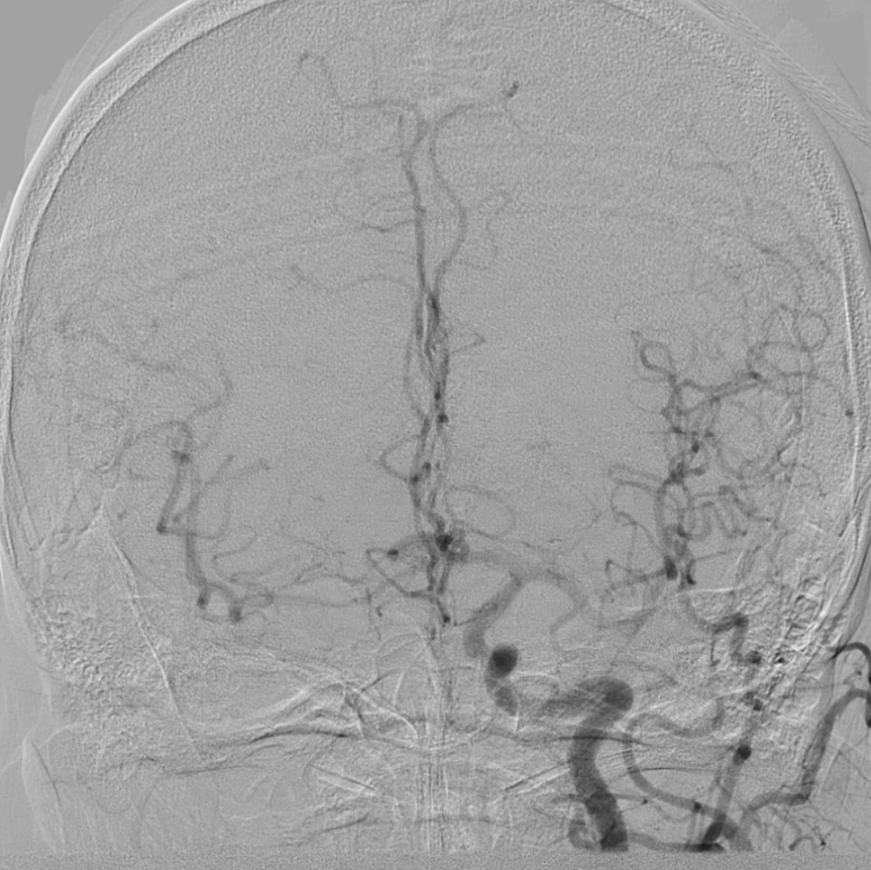

血供改善与安全性验证

造影显示:支架膨胀良好,无需后扩张;

颅内血供:左侧颈内动脉血流通畅,因右侧闭塞,左侧成为全脑主要供血通路,血供恢复满意